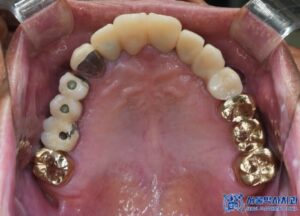

태평동치과 서울박사치과는

원내 기공소에서 보철물을

직접 제작하고 있기 때문에

빠르고 정밀한 보철물 제작이 가능합니다.

특히 10년 이상의 경력을 가진

전문 치과 기공사가 상주하며,

개개인의 구강 구조에 맞춰 정교한 보철물을

제작하기 때문에 기능성과 심미성이 뛰어납니다.

또한, 맞춤형 지대주를 사용하여

음식물 끼임이 적고,

고품질의 내구성이 강한

보철물을 제작하고 있어

장기간 사용하기에도 유리합니다.